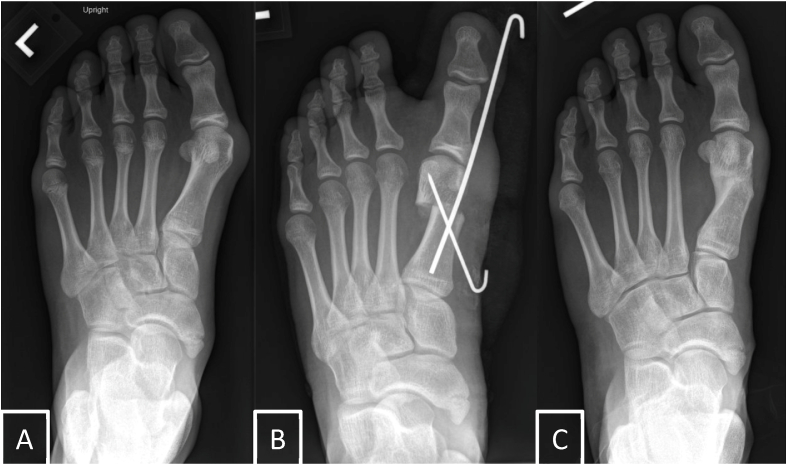

Abstract Image